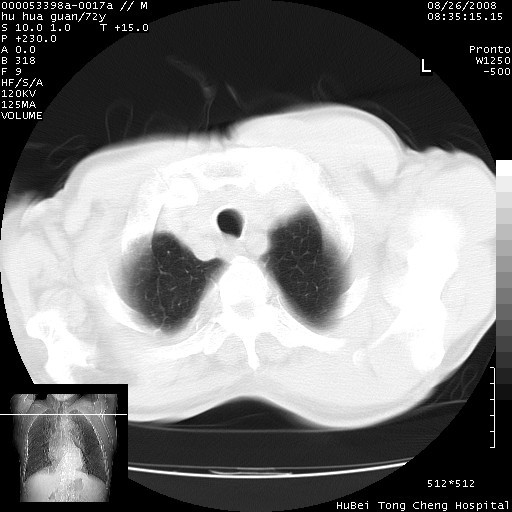

标题: CT15582:M,72Y。请老师帮分析胸部病变。 [打印本页]

标题: CT15582:M,72Y。请老师帮分析胸部病变。

可以明确的说。肯定不是主动脉夹层破裂出血!考虑为淋巴瘤或间叶组织来源的恶性肿瘤可能性大。右肺小结节建议薄层观察,如能发现恶性征象,那椎前改变就考虑为转移所致。至于双侧少量胸水乃静脉血回流受阻所致。

图像及窗宽窗位均不理想。周围性肺癌/胸腔积液/纵隔积液。

1、右肺周围性肺癌、胸腔积液(双)

2、建议食道吞钡和增强检查排除食道和主动脉病变

3、后纵隔淋巴类肿瘤

1、右上肺结节病变,肺泡癌不除外,请随诊;左下肺近后纵隔病变,考虑纵隔型肺癌侵犯大血管可能;

2、右下肺背段少许炎症,双侧胸腔积液,右下肺纤维索条。

降主动脉前移位,后纵隔占位

后纵隔占位,降主动脉前移位;双侧胸腔积液;应排外食管病变侵犯血管可能;